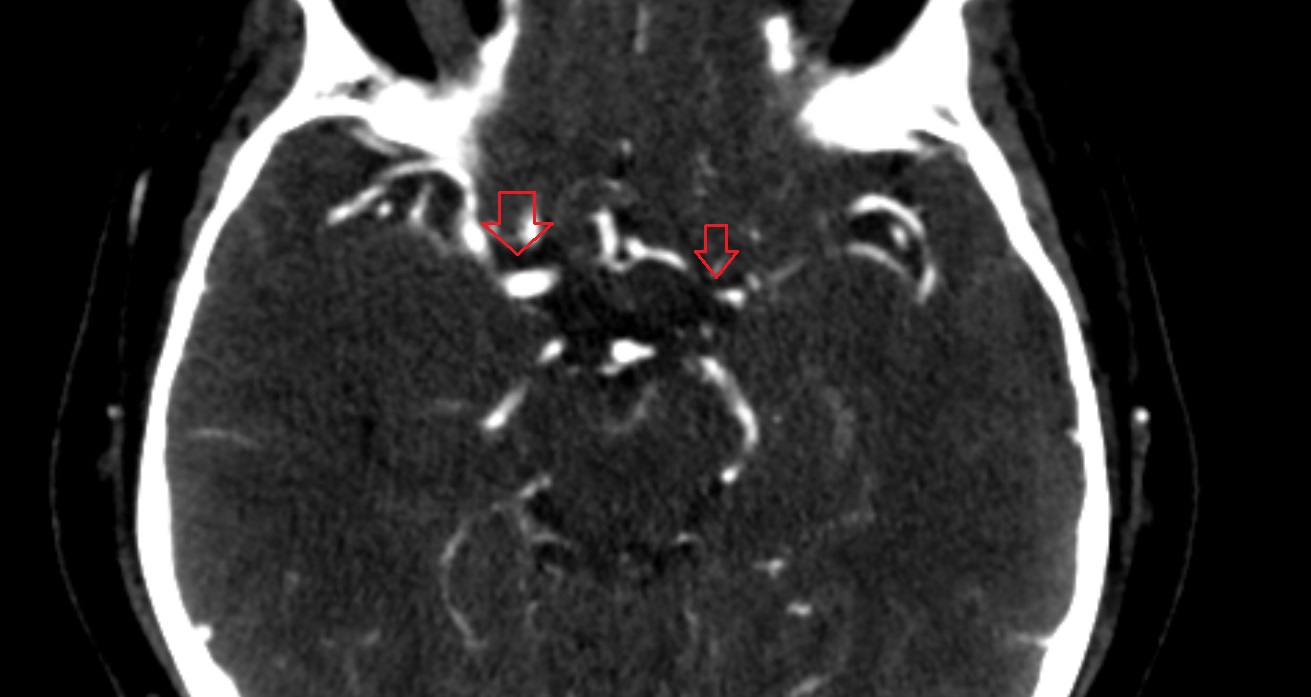

- Cerebellopontine cistern